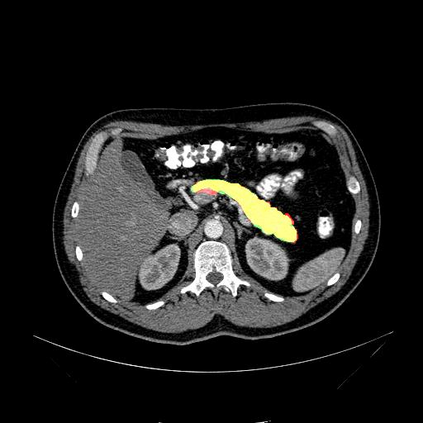

In this paper, we adopt 3D Convolutional Neural Networks to segment volumetric medical images. Although deep neural networks have been proven to be very effective on many 2D vision tasks, it is still challenging to apply them to 3D tasks due to the limited amount of annotated 3D data and limited computational resources. We propose a novel 3D-based coarse-to-fine framework to effectively and efficiently tackle these challenges. The proposed 3D-based framework outperforms the 2D counterpart to a large margin since it can leverage the rich spatial infor- mation along all three axes. We conduct experiments on two datasets which include healthy and pathological pancreases respectively, and achieve the current state-of-the-art in terms of Dice-S{\o}rensen Coefficient (DSC). On the NIH pancreas segmentation dataset, we outperform the previous best by an average of over 2%, and the worst case is improved by 7% to reach almost 70%, which indicates the reliability of our framework in clinical applications.